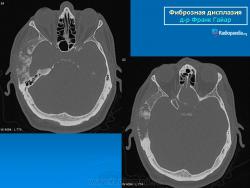

Локализация: для монооссальной фиброзной дисплазии характерно поражение одной из костей лицевого черепа, а также бедренной или большеберцовой кости, реже одного ребра; при полиоссальной фиброзной дисплазии страдают в первую очередь бедренная, большеберцовая и тазовые кости, не исключено и поражение мелких костей стопы, черепа, реже ребер. Рентгенологическая картина фиброзной дисплазии разнообразна. Патологические участки могут быть то более плотными, то более прозрачными по сравнению с окружающей костью, иногда имеют вид «матового стекла». Одни очаги четко отграничены зоной склероза, контуры других расплывчатые, что особенно характерно для костей черепа. Нередко выявляются узуры в кортикальном слое, а при наличии перелома — отчетливая периостальная реакция. При макроскопическом исследовании определяются беловато-красные опухолевые очаги разной плотности, в зависимости от степени выраженности их минерализации. Имеются многочисленные кисты, заполненные желтоватой или красноватой жидкостью, и полупрозрачные участки хряща до 3 см в диаметре.

Для фиброзной остеодисплазии, или болезни Брайцева-Лихтенштейна, характерно нарушение костеобразующей функции мезенхимы, проявляющееся в одной или нескольких костях, что ведет к их деформации и образованию в них очагов разрежения, обычно отграниченных от здоровой ткани кости склеротической каймой. Объем пораженной кости при этом может быть увеличен. Чаще поражаются трубчатые кости, но характерные изменения могут отмечаться и в костях черепа. В таких случаях возможны облитерация придаточных полостей носа, деформация глазниц, сужение отверстий в основании мозгового черепа и в лицевом черепе, ведущее к нарушению функции проходящих через них нервов и сосудов. Заболевание, возможно, наследственное, проявляется с детских лет. Описал в I927 г. отечественный хирург В.Р. Брайцев (1878-1964), несколько позже - американский патологоанатом L. Lichtenstein (1906-1977).